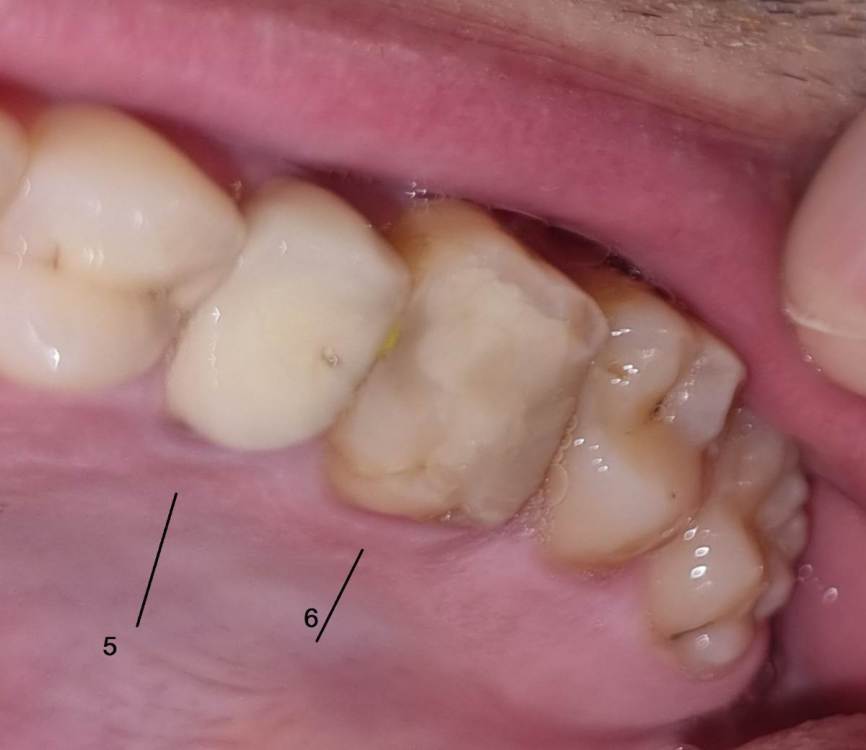

Chelovek2012 Опубликовано 17 апреля, 2023 Поделиться Опубликовано 17 апреля, 2023 (изменено) Всем добрый день. У меня вопрос. Верхняя левая 6-ка: Зуб давно был с запломбироваными каналами. Месяц назад их перепломбировали. Вкрутили в середину зуба какие-то как шурубчики для укрепления. И доктор говорит, что будет коронка Можно ли поборотся и спасти зуб, в который уже вкручены шурупчики для укрепления? 3 стенки зубы точно вижу на фото. Или нету смысла и он разлетится? Пломбировать уже нету смысла? Или технология пломбирования уже тут не подходит? 5 зуб возле него. Врачь говорит сразу сменить и эту коронку (ей 10 лет), так как между зубами есть нестыковка - темное место на рентгене между зубами Изменено 17 апреля, 2023 пользователем Chelovek2012 Ссылка на комментарий

DoctorT Опубликовано 18 апреля, 2023 Поделиться Опубликовано 18 апреля, 2023 (изменено) Коронка и ставиться, чтобы побороться за этот зуб, в противном случае (при таком объеме пломбы) вы его потеряете рано. Кстати, если вы перепроверяете слова вашего доктора, рекомендую вам сменить доктора на того, кому вы будете доверять. Изменено 18 апреля, 2023 пользователем DoctorT Ссылка на комментарий

DoctorT Опубликовано 19 апреля, 2023 Поделиться Опубликовано 19 апреля, 2023 1 час назад, Chelovek2012 сказал: А это касается и других зубов, у которых есть только стенки? Нету технологии спасти зуб (во своих стенках) без коронки? Вы не бойтесь коронки, они же бывают разные, главное сделать грамотно и чтобы прилегание было отличное, такая коронка может прослужить очень долго. Поймите, что если убрать весь пломбировочный материал с зуба, то от него ничего не останется. Коронка только армирует ваши оставшиеся стенки и пломбу, как деревянную бочку армируют железные кольца... 1 Ссылка на комментарий